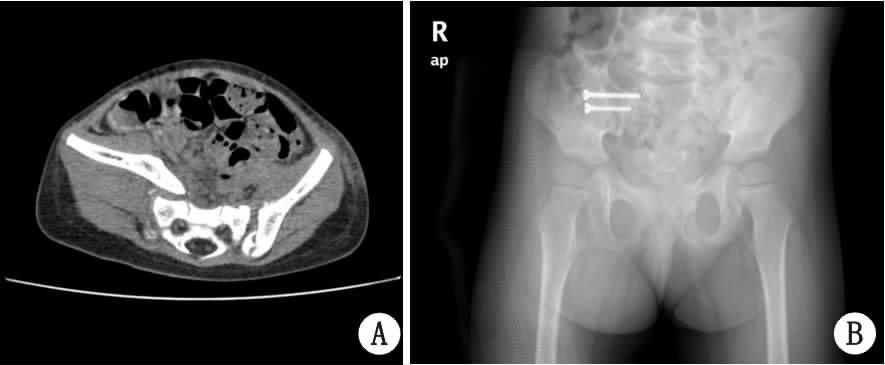

| A:CT示,右侧骶髂关节骨折脱位,移位明显;B:术后X线片示,右侧骶髂关节予解剖复位,2枚螺钉固定 图 2 女,3岁 |